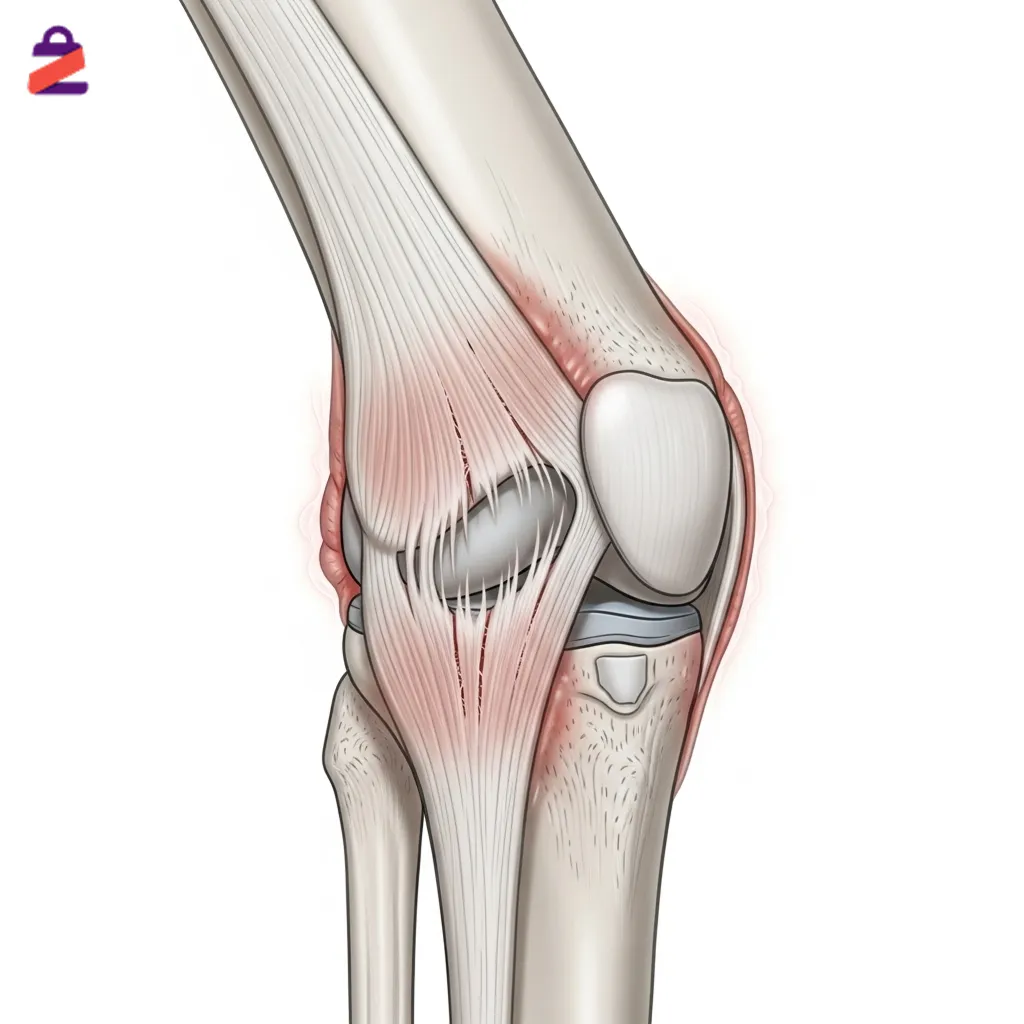

کشیدگی رباط زانو: علل، علائم و روشهای پیشگیری و درمان

کشیدگی رباط زانو یکی از آسیبهای شایع مفصل زانو است که میتواند ورزشکاران و افراد عادی را تحت تأثیر قرار دهد. رباطهای زانو وظیفه پایداری و کنترل حرکت مفصل را دارند و فشار ناگهانی یا حرکت اشتباه میتواند باعث کشیدگی آنها شود. این آسیب با درد، تورم و محدودیت حرکت همراه است و شناخت علائم […]